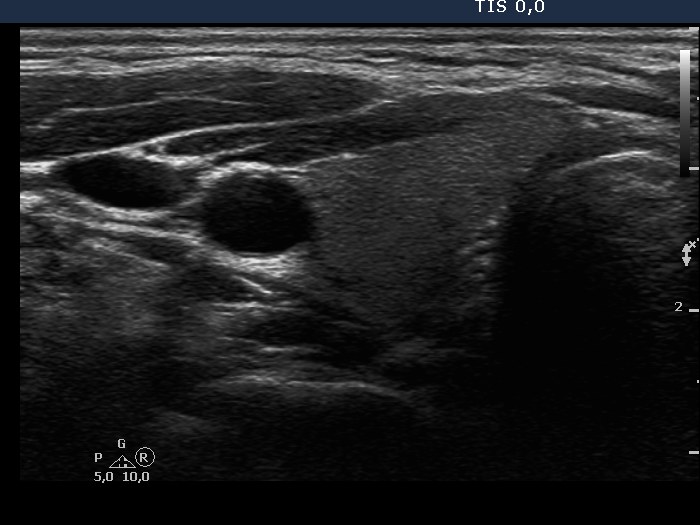

Ultrasonography: the thyroids were intact, i.e. the basic echo structure was echonormal and only a few small hypoechogenic areas were found. The echogenicity index was less than 1%. The vascularization was not specific.